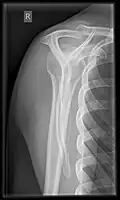

Fractures of shoulder bones can include clavicular fractures, scapular fractures, and fractures of the upper humerus.

X-ray

Projectional radiography views of the shoulder include:

- AP-projection 40° posterior oblique after Grashey

The body has to be rotated about 30 to 45 degrees towards the shoulder to be imaged, and the standing or sitting patient lets the arm hang. This method reveals the joint gap and the vertical alignment towards the socket.[26]

- Transaxillary projection

The arm should be abducted 80 to 100 degrees. This method reveals:[26]

- The horizontal alignment of the humerus head in respect to the socket and the lateral clavicle in respect to the acromion

- Lesions of the anterior and posterior socket border, or of the tuberculum minus

- The eventual non-closure of the acromial apophysis

- The coraco-humeral interval

- Y-projection

The lateral contour of the shoulder should be positioned in front of the film in a way that the longitudinal axis of the scapula continues parallel to the path of the rays. This method reveals:[26]

- The horizontal centralization of the humerus head and socket

- The osseous margins of the coraco-acromial arch and hence the supraspinatus outlet canal

- The shape of the acromion

This projection has a low tolerance for errors and, accordingly, needs proper execution.[26] The Y-projection can be traced back to Wijnblath’s 1933 published cavitas-en-face projection.[27]

-

CR. shoulay film. -

Transaxillary conventional radiography -

Y-projection conventional radiography